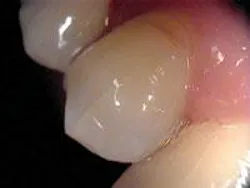

Treatment of the tooth depends on the degree of pulpal involvement and the extent of the crack. Those cracks, which are visualized but remain asymptomatic and clinical testing (such as percussion, palpation, mobility, probing, and thermal testing) is within normal limits, should be treated with a crown or some other form of complete cuspal coverage (see Figure 3). This is to prevent further propagation of the crack and the onset of symptoms. However, if a patient exhibits more extensive symptoms from the start, including increased sensitivity to thermal provocation and percussion/biting, root canal therapy should be performed prior to placement of a crown. These are considered incomplete vertical root fractures. A study by Kahler8 showed that all symptomatic cracks in teeth appeared to extend right through the dentin to the dentino-enamel junction and were extensively contaminated by bacteria. Hence, root canal therapy and crowning for all symptomatic cracks are recommended.